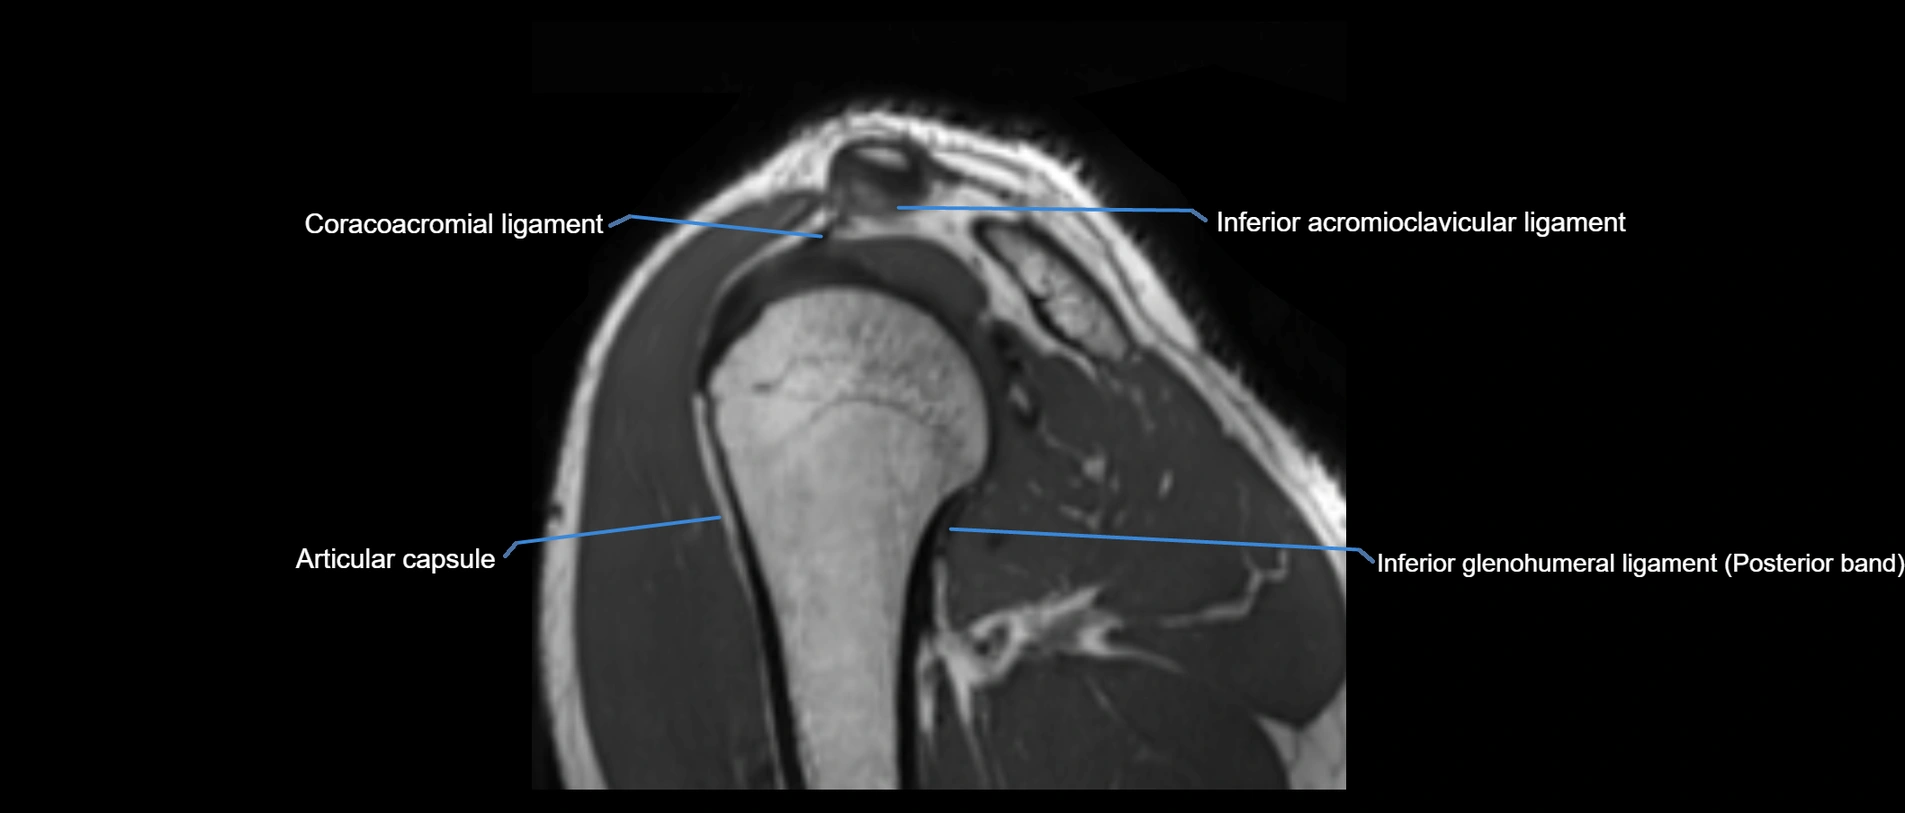

MRI images

image